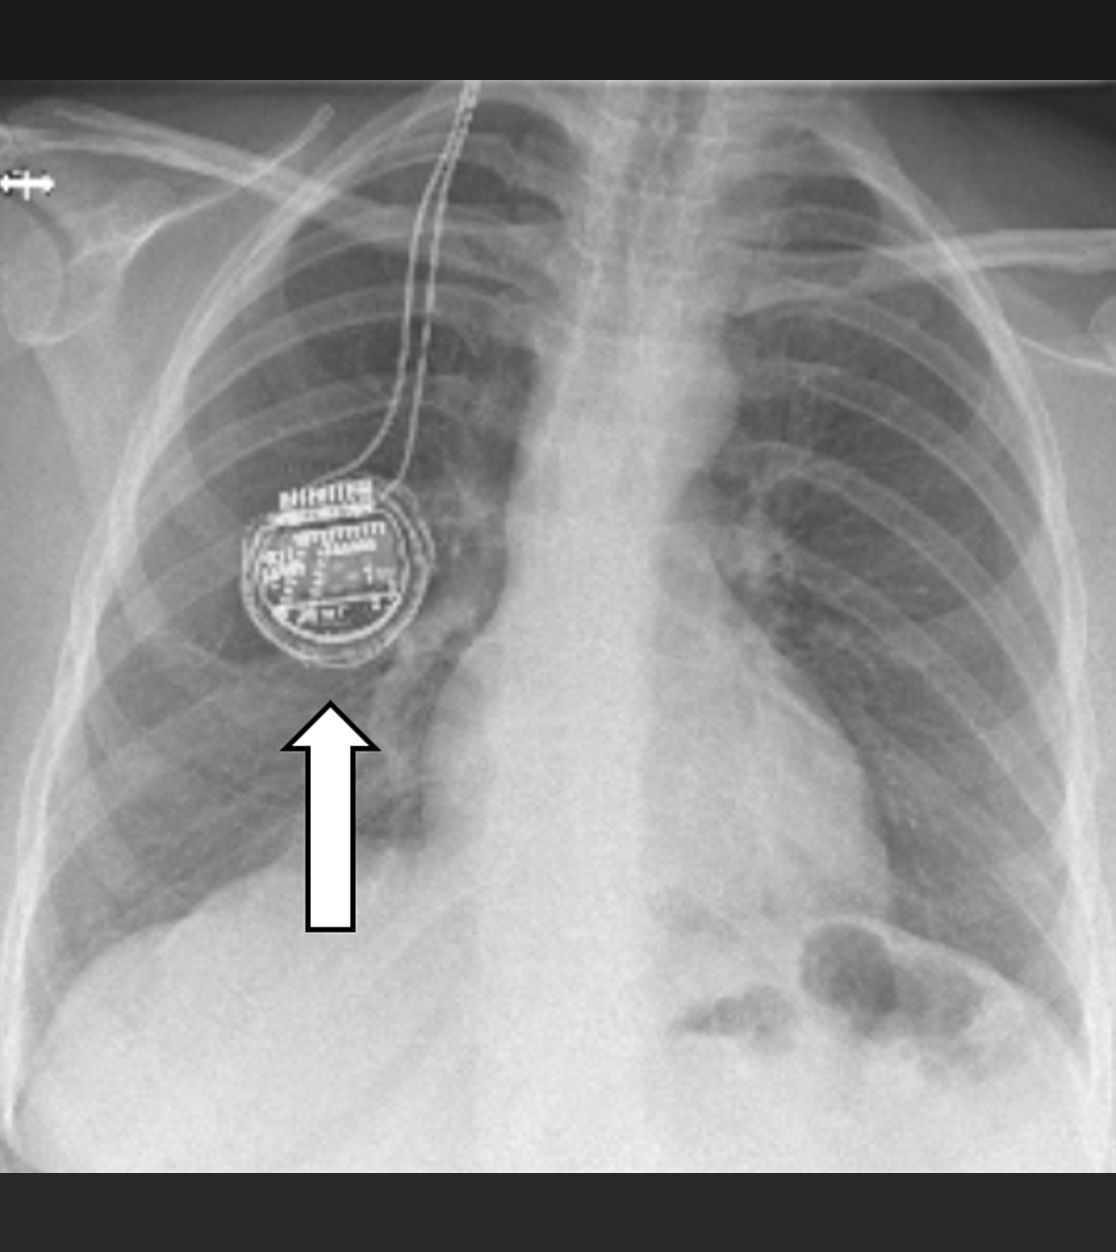

Die Tiefe Hirnstimulation, welche meist für Patienten mit Bewegungsstörungen wie Parkinson oder einer Dystonie eingesetzt wird, kann auch bei Patienten mit chronischen Gesichtsschmerzen oder einem sog. zentralen Schmerz zur Anwendung kommen. Es werden Elektroden gezielt mittels sog. stereotaktischer und robotischer Verfahren in kleine Kerngebiete des Gehirns implantiert und – wie bei anderen neuromodulativen Verfahren – an einen Impulsgeber (vergleichbar mit einem Herzschrittmacher) angeschlossen. Durch die Abgabe angepasster elektrischer Impulse sollen dann die Schmerzen gelindert und somit die Lebensqualität der Patienten verbessert werden. Wie bei der Motorcortexstimulation muss die Möglichkeit einer Tiefenhirnstimulation zur Schmerztherapie stets individuell evaluiert werden.

Impulsgeber im Bereich des Brustkorbs